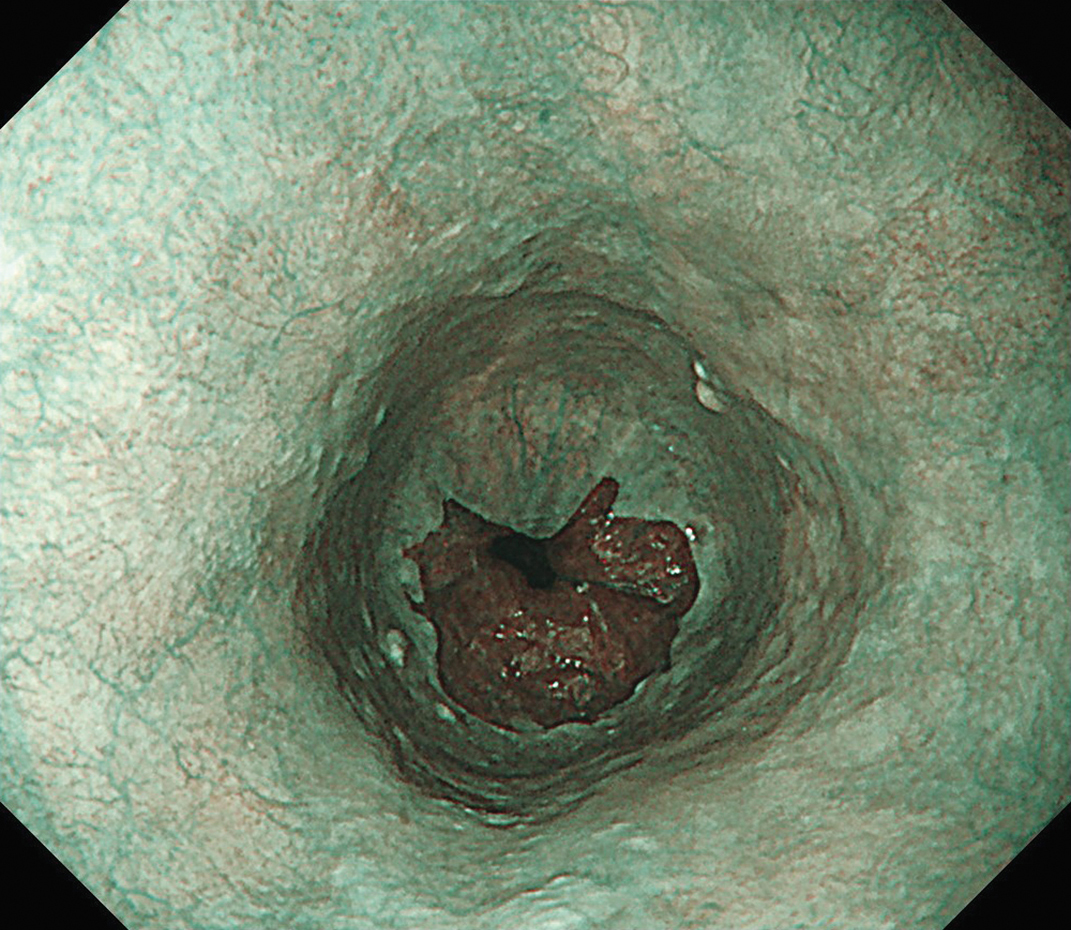

EVIS X1×GIF-1200N 症例画像

下部食道 NBI